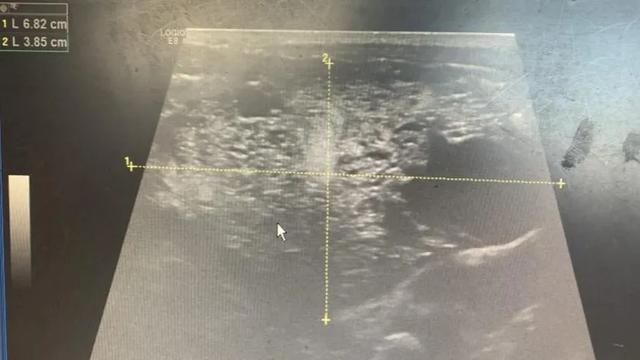

b超(左腹部肿块)

近日,一位来自宁德的宝妈带着10天大的黄疸宝宝来到福建医科大学附属福州儿童医院。令人惊讶的是,经腹b超显示孩子左腹部有一个巨大的肿瘤,但CT显示肿瘤位于右腹部。突如其来的变化吓坏了孩子的母亲。肿瘤在哪里?为什么检查结果自相矛盾?

通过对患儿详细的身体检查和CT片的解读,肿瘤外科主任刘升表示,这是一个位于腹腔内的“移动”肿瘤,因为肿瘤位于肠系膜,它会随着肠的肠系膜轴左右摆动。